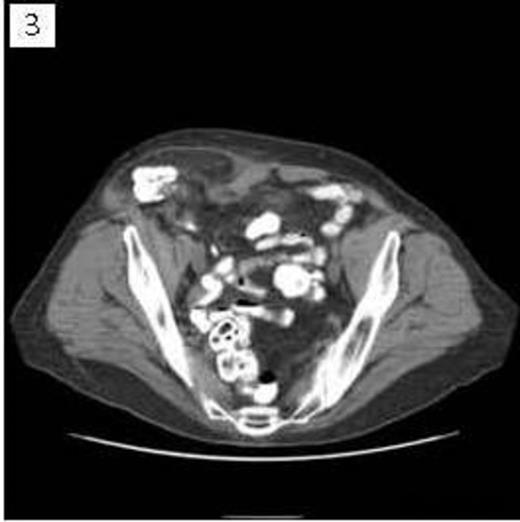

A 68 year old female presented to clinic with a several year history of right lower quadrant abdominal discomfort and “bulge”. Physical exam demonstrated a reducible mass originating in the inguinal region that tracked cephalad above the level of the inguinal ligament. CT imaging revealed a large inguinal hernia defect (Figure 1) with herniated bowel coursing 13cm cephalad between the external and internal abdominal oblique muscles (Figure 2 & 3).